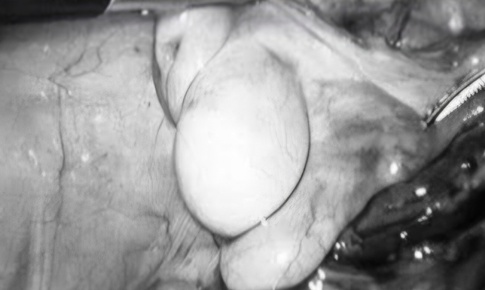

Camera bệnh viện - 26/06/2025 21:33SKĐS - Ca mổ được thực hiện bằng phương pháp nội soi ổ bụng hiện đại, giúp đưa tinh hoàn về đúng vị trí trong bìu, loại bỏ nguy cơ vô sinh và ung thư tinh hoàn.